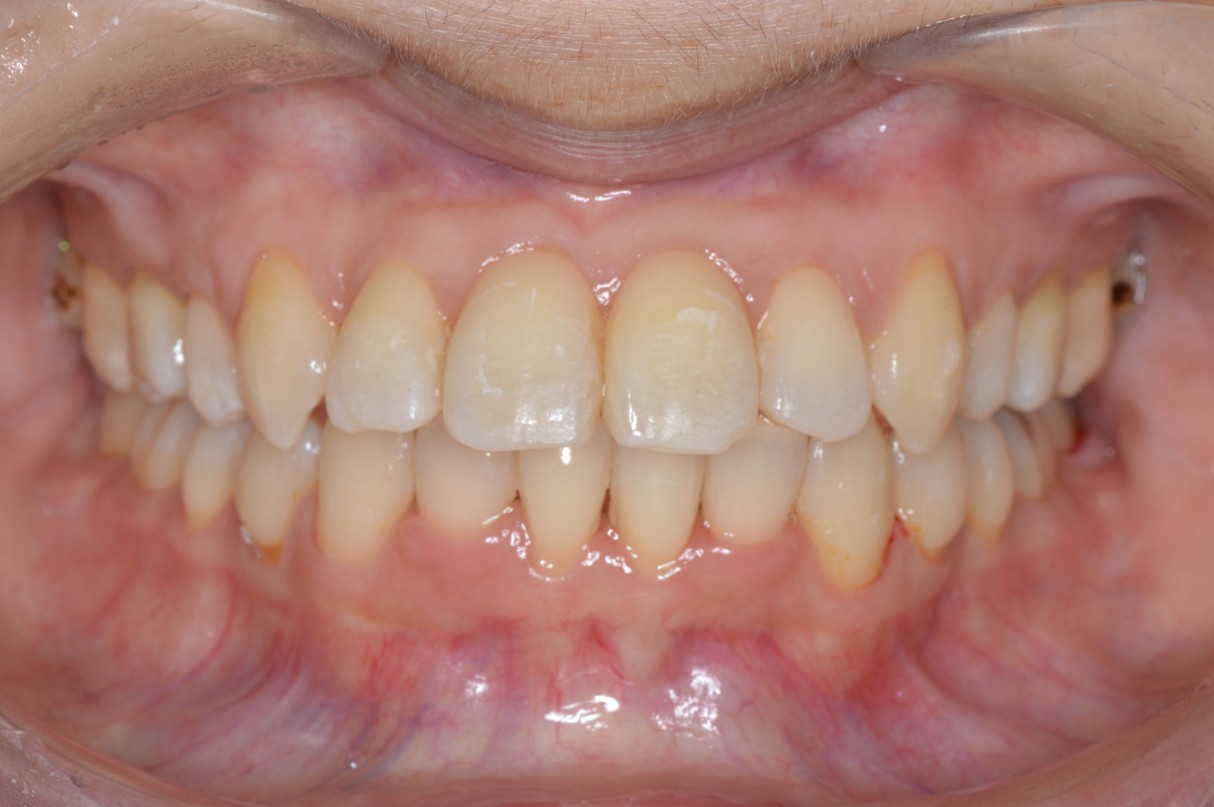

症例1

| 項目 | 詳細 |

|---|---|

| 患者様データ | 30代 女性 |

| 来院時の主訴 | 「上下のガタガタ歯並びと噛み合わせが気になる。」 |

| 矯正法 | 上の歯2本を抜歯しての矯正 |

| 通院期間 | 2年9ヶ月 |

| 治療費 | 総額:1,070,000円(税抜) 【内訳】 精密検査50,000円、メタルワイヤー矯正800,000円、月に1度の調整料5,000円、後戻り防止のリテーナー35,000円×2 |

| リスクと副作用 |

①歯を動かす事による痛みがあります。また、装置に慣れるまでは、口内炎ができやすいです。 ②歯肉が退縮するリスクがあります。装置が全ての歯に付くので、ハミガキが難しくなります。 ③長期的なメインテナンスが必要 |

| ここがこだわりのポイント!☝ |

この患者様の場合、歯並びのガタガタが強かったことや、抜歯したスペースを埋めるのに時間がかりました。ホームケアも大変だったと思いますが、とてもきれいな歯並びに改善することができました。 |